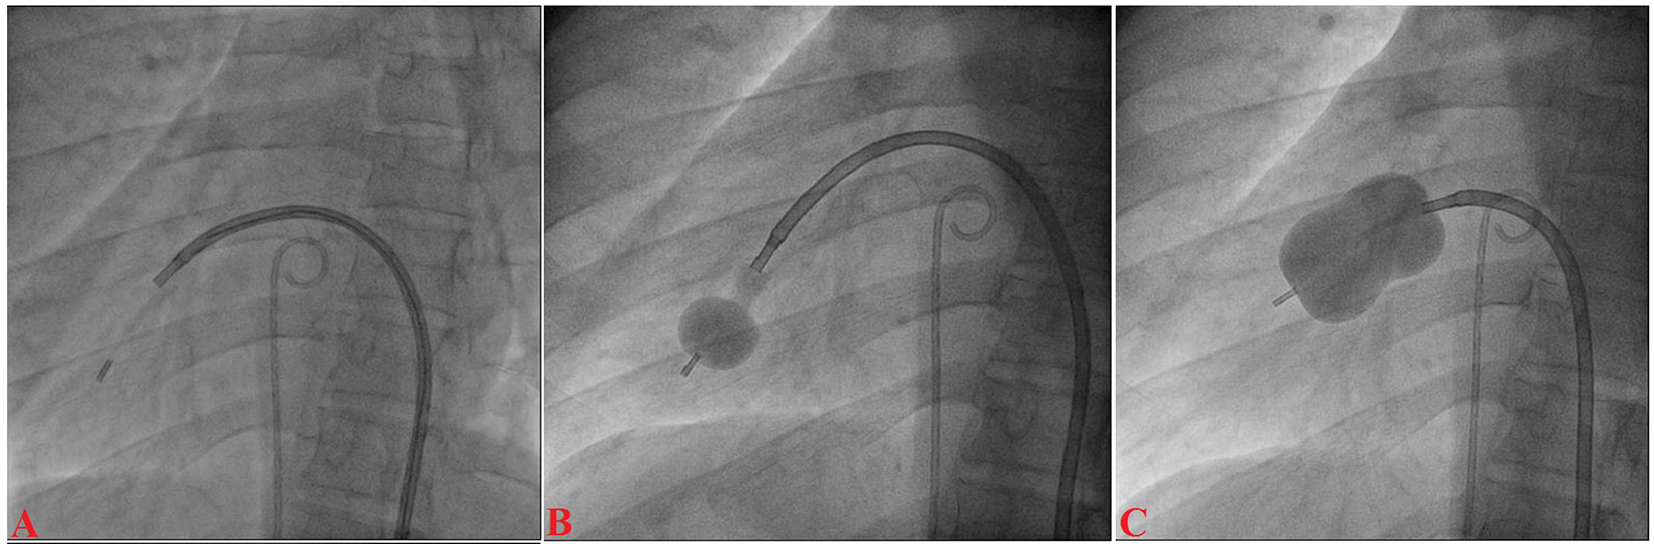

A 12-year-old boy presented with progressive exertional dyspnea NYHA class III of 7 months duration. Blood pressure was 100/76 mm Hg in right arm in supine position. Pulse rate was 70/min, regular, low volume, with no special character with all peripheral pulses palpable. Jugular venous pulse pressure was elevated 6 cm above sternal angle with prominent a wave and v-y descent. Apex beat was located in right fifth intercostals space, tapping in character. There was grade II right parasternal heave. P2 was palpable. S1 was loud. S2 was loud; loud P2 component with narrow split. Opening snap (OS) was present with narrow A2-OS gap. There was long grade IV mid diastolic rumbling murmur with presystolic accentuation. Pansystolic murmur grade III/VI of tricuspid regurgitation was present in left parasternal area. The electrocardiograph (ECG) showed inverted P wave in all leads except aVR and V1, upright R wave in aVR, reduction in the R wave voltage across the chest leads with evidence of right ventricular hypertrophy (Fig. 1A). Chest X-ray PA view showed dextrocardia (Fig. 1B). Subcotal window showed aorta on the right and inferior vena cava on the left side, i.e. situs inversus (Fig. 1C). Transthoracic echocardiography showed critical mitral stenosis with mitral valve area (MVA) of 0.6 cm2 by pressure half time (Fig. 1D) and planimetry (Fig. 1E) and mild mitral regurgitation. His Wilkin’s score was 8/16 (C2, T2, M2, S2). Mean gradient across mitral valve was 36 mm Hg. Transesophageal echo ruled out any LA or LAA clot. Dextrocardia, atrio-ventricular (AV) and ventriculo-arterial (VA) concordance were present. Left femoral artery and venous access was obtained with a 5F arterial and 8F venous sheaths, respectively after proper consent. A 5F pigtail catheter was passed retrograde into the aorta and parked in the non-coronary sinus of the aortic root. A 0.035" J-tip guide wire was then passed up the femoral vein into the inferior vena cava (IVC) and up into the left-sided superior vena cava (SVC) via the left-sided “right atrium” (Fig. 2A). An 8F Mullins sheath was passed up on the guide wire, into the left SVC (Fig. 2B). A curved Brockenbrough septal puncture needle was introduced into the sheath stopping just short of the tip and was oriented to 9 o’clock position in the SVC. Septal descent was done by withdrawing the needle and the sheath in tandem into the heart with the needle pointer in 9 o’clock position. Septal puncture was done in right anterior oblique (RAO) 40° and also confirmed in left lateral projection which was contrary to our conventional view, i.e., left anterior oblique (LAO) 40° projection (Fig. 2C). LA was entered and pressure was recorded. The septum was dilated and heparin 100 IU/kg IV was given. A “loopy” LA wire was then passed through the sheath into LA and the latter was withdrawn leaving the LA wire inside (Fig. 2D). The 14F dilator was then used to dilate the septum (Fig. 3A). Subsequently, the accura balloon (Vascular Concepts, Essex, UK) was introduced over the LA wire to enter the LA (Fig. 3B). The LA wire was withdrawn and the balloon was flushed and simultaneous LA/LV pressures were recorded. Now, director was used to guide the balloon (Fig. 3C) towards mitral valve by slight counter clock rotation till flip at the balloon tip was noted (Fig. 3D). Director was pulled and balloon was pushed in a symphony to facilitate its entry into the LV (Fig. 4A). Mitral valve was negotiated and dilation was performed successfully in LAO 40° projection which was contrary to our conventional view, i.e., RAO 40° projection (Fig. 4B, C). Post-procedural MVA was 2.0 cm2 and MR still remained mild (Fig. 1F). Patient was discharged in stable condition on third day.

![]() Click for large image | Figure 4. Accura balloon entering into the LV (A); distal inflation of balloon (B); mitral valve dilation (C). |